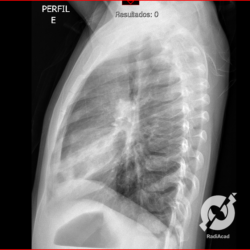

E o nome dado a esta alteração radiográfica que corresponde à substituição do ar alveolar por líquido é a consolidação alveolar.

Uma consolidação alveolar é, por definição, uma opacidade (imagem densa, branquinha) homogênea ou às vezes heterogênea (pela presença de calcificações ou cavidades), de limites mal definidos, exceto quando toca a pleura da parede ou das cissuras pulmonares. É um termo usado tanto em radiografia, como em tomografia computadorizada. Na tomografia, um outro termo é usado: vidro fosco, que é uma opacidade (branquinha mas não tanto como a consolidação), que borra o pulmão mas deixa ver os vasos de permeio (igual bigode de adolescente: dá pra ver todo o fundo).

Nós vamos mostrar aqui um pequeno apanhado de pneumonias de variados agentes, em diversos segmentos e lobos pulmonares, com extensões variadas. O objetivo é identificar o padrão radiológico de consolidação alveolar e não determinar o agente infeccioso, isso vai ser assunto para mais adiante. Aliás já antecipo que é fundamental saber localizar a lesão, porque alguns destes bichos gostam de determinados segmentos, alguns tumores também têm as suas preferências, então localização é fundamental. Se localização não fosse importante, um apartamento na beira do mar sairia o mesmo preço de um apartamento de frente pra BR-101, concordam?

Seguem alguns dos nossos casos de pneumonia para vocês treinarem os olhos e não se apavorarem nos plantões.